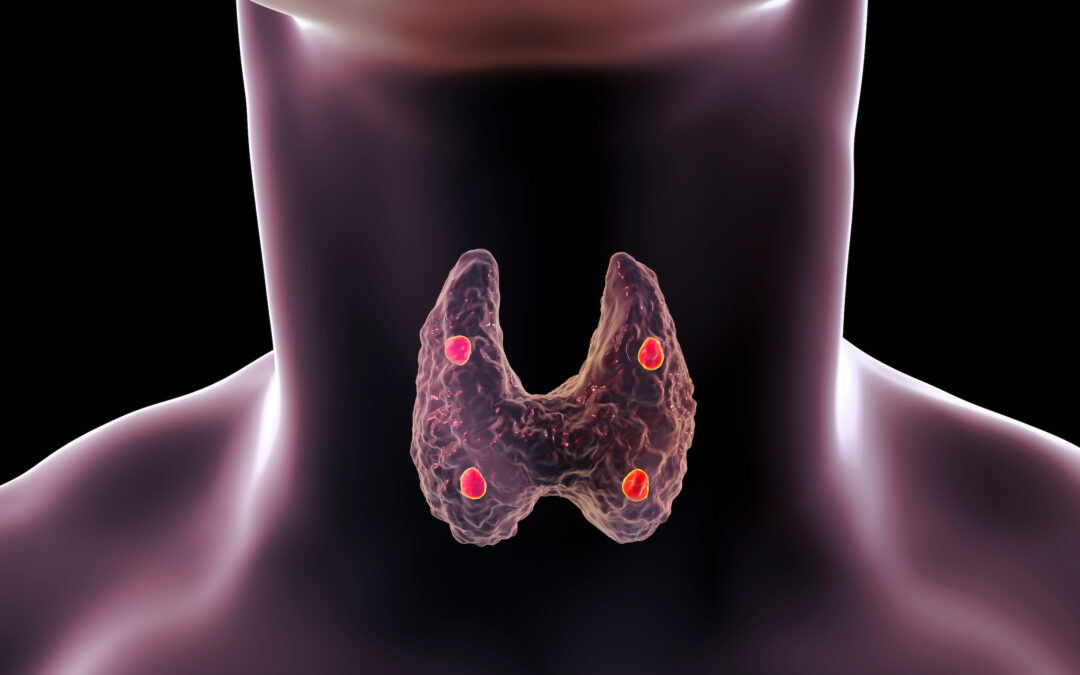

Όλοι οι Παραθυρεοειδείς αδένες μας διαθέτουν έναν ενσωματωμένο «θερμοστάτη» (όλοι οι ενδοκρινείς αδένες διαθέτουν ! ).

Ο «θερμοστάτης αυτός είναι πολύ ευαίσθητος στα επίπεδα ασβεστίου στο αίμα.

Το φυσιολογικό εύρος των τιμών ασβεστίου για τον «θερμοστάτη» είναι (8,5-10,2mg/dl).

Οι φυσιολογικοί Παραθυρεοειδείς αδένες ελέγχουν συνεχώς τα επίπεδα ασβεστίου στο αίμα. Μόλις τα επίπεδα ασβεστίου πέφτουν, οι Παραθυρεοειδείς αδένες ξεκινούν να παράγουν παραθορμόνη.

Στη πλειοψηφία των ασθενών με υπερπαραθυρεοειδισμό, υπάρχει ένας παθολογικός Παραθυρεοειδής και τρείς φυσιολογικοί.

Ο παθολογικός Παραθυρεοειδής αδένας είναι κολλημένος στη θέση «on», οι υπόλοιποι όμως των οποίων ο «θερμοστάτης» λειτουργεί φυσιολογικά, αναγνωρίζουν τις αυξημένες τιμές ασβεστίου στο αίμα και σταματούν να παράγουν παραθορμόνη («off»).